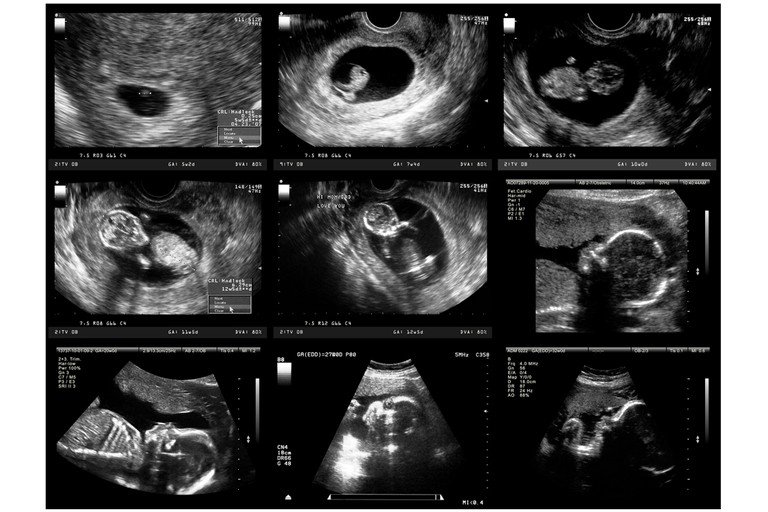

Ультразвукове дослідження може показати вагітність на досить ранніх термінах, але це залежить від декількох факторів. Найраніше, коли УЗД може підтвердити вагітність, це приблизно 4-5 тижнів після зачаття. На цьому етапі може бути видно лише маленький міхур, заповнений рідиною (гестаційний мішок) всередині матки.

- Гестаційний мішок: Бачимий на УЗД зазвичай на 4-5 тижні вагітності.

- Жовтковий мішок: Підтверджує наявність вагітності, з’являється приблизно на 5-6 тижнях.

- Серцевий ритм плоду: Може бути зафіксований приблизно на 6-7 тижнях вагітності.

- Розвиток плоду: На 8-12 тижнях можна чітко бачити розвинуті кінцівки і рухи плоду.